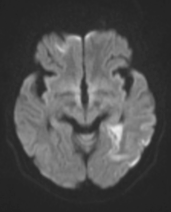

张女士被紧急送往附近医院,头颅磁共振检查明确诊断为急性脑梗死。

医生第一时间为她进行了静脉溶栓治疗 —— 这是脑梗死黄金溶栓时间窗内的常用治疗方式,可治疗后她的症状并没有明显好转。